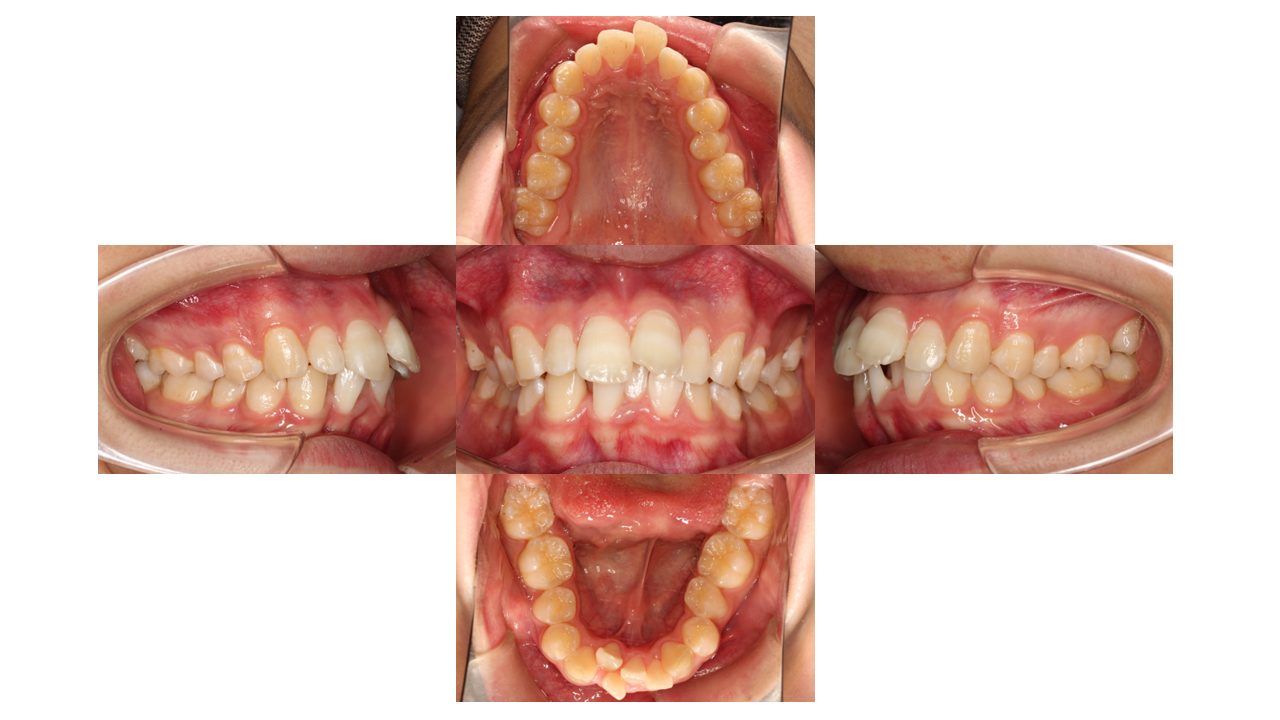

初診時の口腔内の状態です。

上下前歯の凸凹・前歯が出ていることにお悩みでご来院されました。